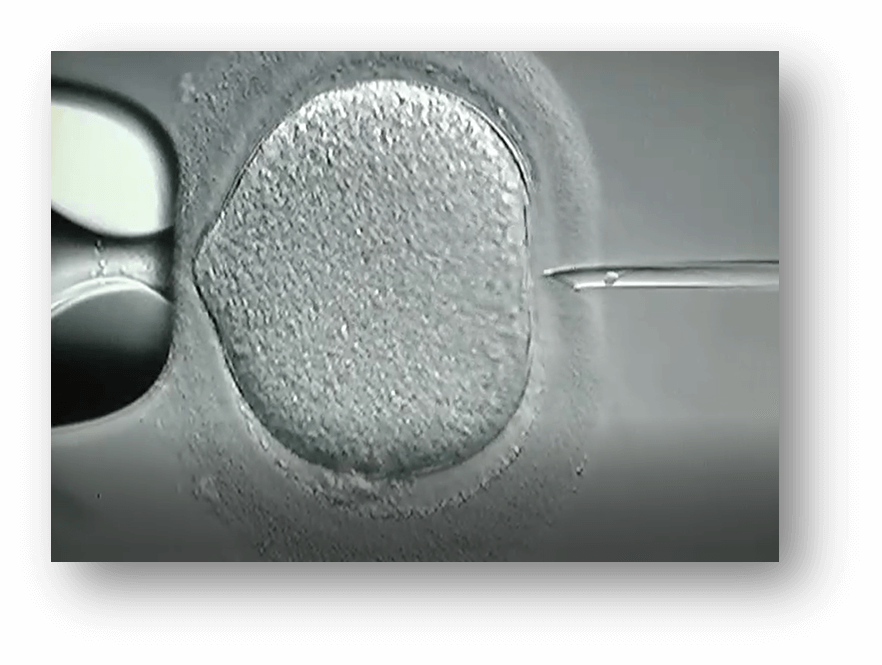

Il razionale è quello di utilizzare la tecnica nota come ICSI, il cui acronimo inglese significa “Intra Cytoplasmic Sperm Injection”, nel trattamento dei problemi insormontabili della fertilità di origine maschile. Questa tecnica prevede sempre la fecondazione in vitro, utilizzando gli spermatozoi selezionati e crioconservati di donatore.

Con l’ICSI è necessario un solo spermatozoo per ovocita. Una volta fecondato, l’ovocita dà origine all’embrione e viene trasferito in utero dove potrà continuare il suo sviluppo.

Il prelievo degli ovociti avviene tramite puntura ed aspirazione dei follicoli. Si tratta di una procedura che richiede sedazione anestesiologica generale. Una volta prelevati, gli ovociti sono conservati alcune ore in un mezzo di coltura mentre si esegue la preparazione del liquido seminale per isolare gli spermatozoi mobili. Se la tecnica da utilizzare è l’ICSI (microiniezione intracitoplasmatica di uno spermatozoo per ovocita maturo), gli ovociti vengono denudati, ossia vengono rimosse le cellule circostanti la superficie, e viene iniettato all’interno di ciascuno un singolo spermatozoo. Nel nostro centro si pratica la ICSI in un’alta percentuale di casi, salvo laddove diversamente indicato. Nel caso in cui si pratichi una fecondazione in vitro classica (FIVET) gli spermatozoi (tra 50.000 e 100.000) sono inseriti nel mezzo di coltura in cui si trovano gli ovociti e, il giorno seguente, si verifica quanti di essi siano stati fecondati. Ovviamente, maggiore è il numero di ovociti e migliore è la qualità dello sperma, maggiore sarà la possibilità di ottenere embrioni